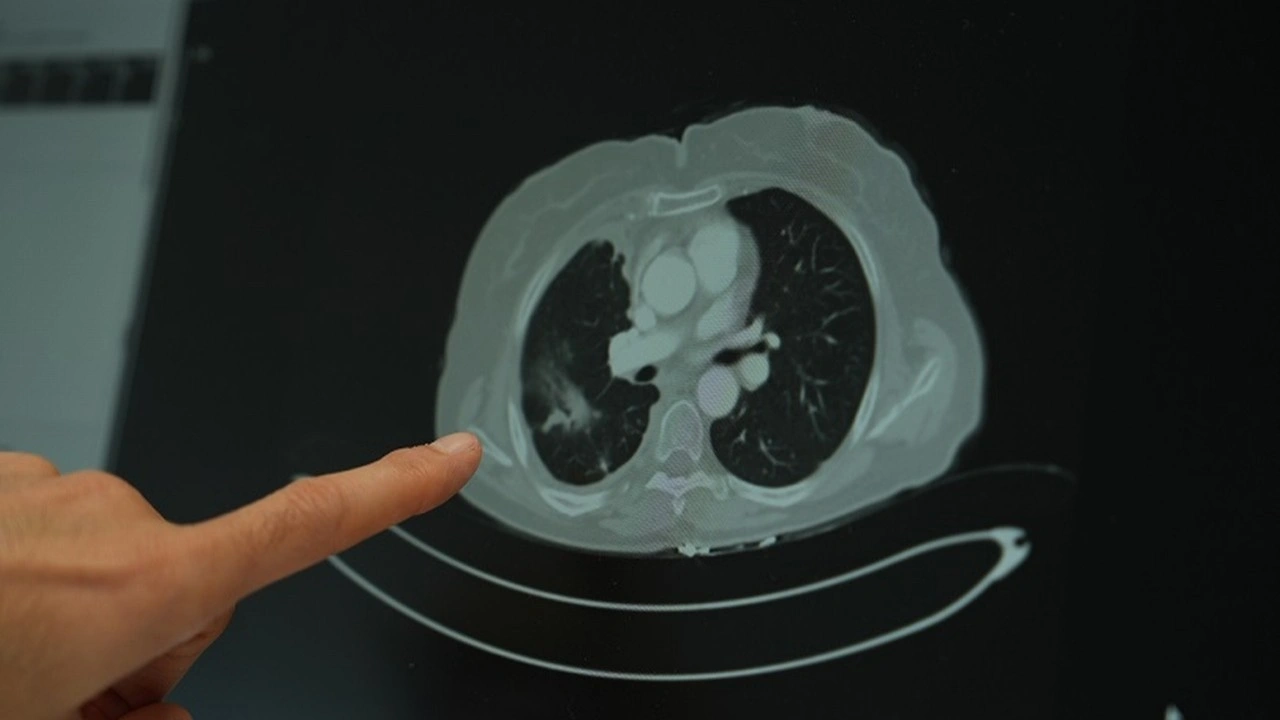

Sigara kullanımının akciğer kanseri üzerindeki etkisini değerlendiren Doç. Dr. Şimşek, uzun süre sigara kullanan kişilerde düşük doz radyasyonla yapılan tomografi taramalarının önerildiğini belirterek “Sigara içen bireylerde akciğer kanseri riski yüksek. Bu nedenle düşük doz radyasyonlu taramalar, erken tanı açısından önemli” ifadelerini kullandı.